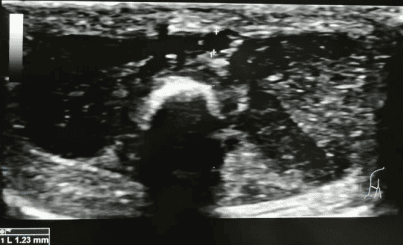

En la siguiente imagen de la izquierda podemos observar la colocación del transductor en plano longitudinal sobre la guía de nitinol en un neonato de 1300g. En la imagen ecográfica podemos observar la guía hiperecogénica en el interior de la luz del vaso corroborando la correcta canalización y permitiendo progresar al siguiente paso de la técnica.